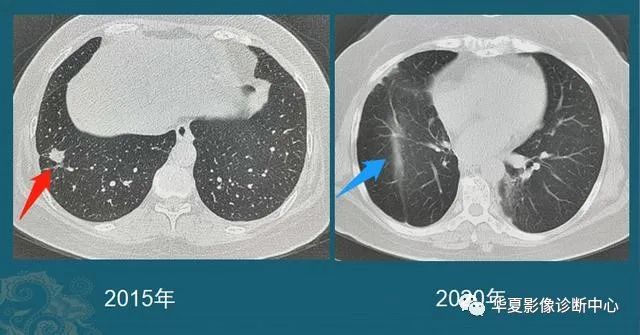

何医生介绍,三代EGFR-TKI伏美替尼由于化学结构上的优化,具备提高药物浓度而不增加副反应的可能,国内外有相似的研究报道。因此,建议李先生开始口服“双倍剂量伏美替尼”靶向治疗。令人欣喜的是,1个月后复查,李先生肺部及肝脏转移灶较前明显退缩,疗效评价达到部分缓解。

双肺粟粒样转移和肝脏转移明显缩小

目前,李先生仍在口服“双倍剂量伏美替尼”治疗,肿瘤控制良好,已经维持稳定近一年,且并未有副作用,目前患者生活质量良好。